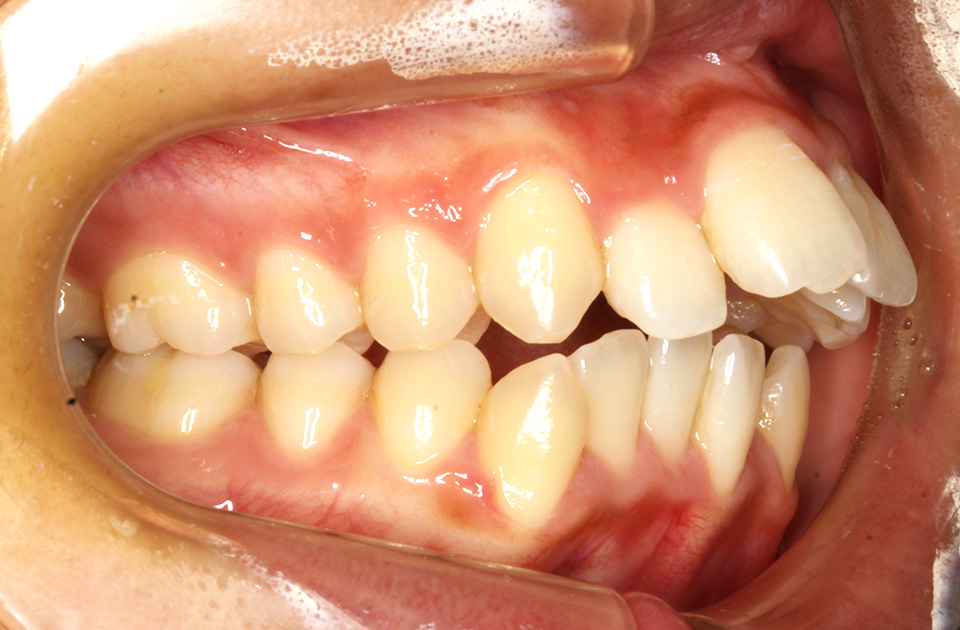

矯正後

矯正後 左側

主訴 前歯で物が咬めない、歯並びの凸凹、出っ歯を治したい

年齢 20代

治療法 上下顎マルチブラケット装置、歯科矯正用アンカースクリュー

抜歯の有無 上顎左右側第一小臼歯、下顎左右側第二小臼歯

治療期間 1年10ヶ月